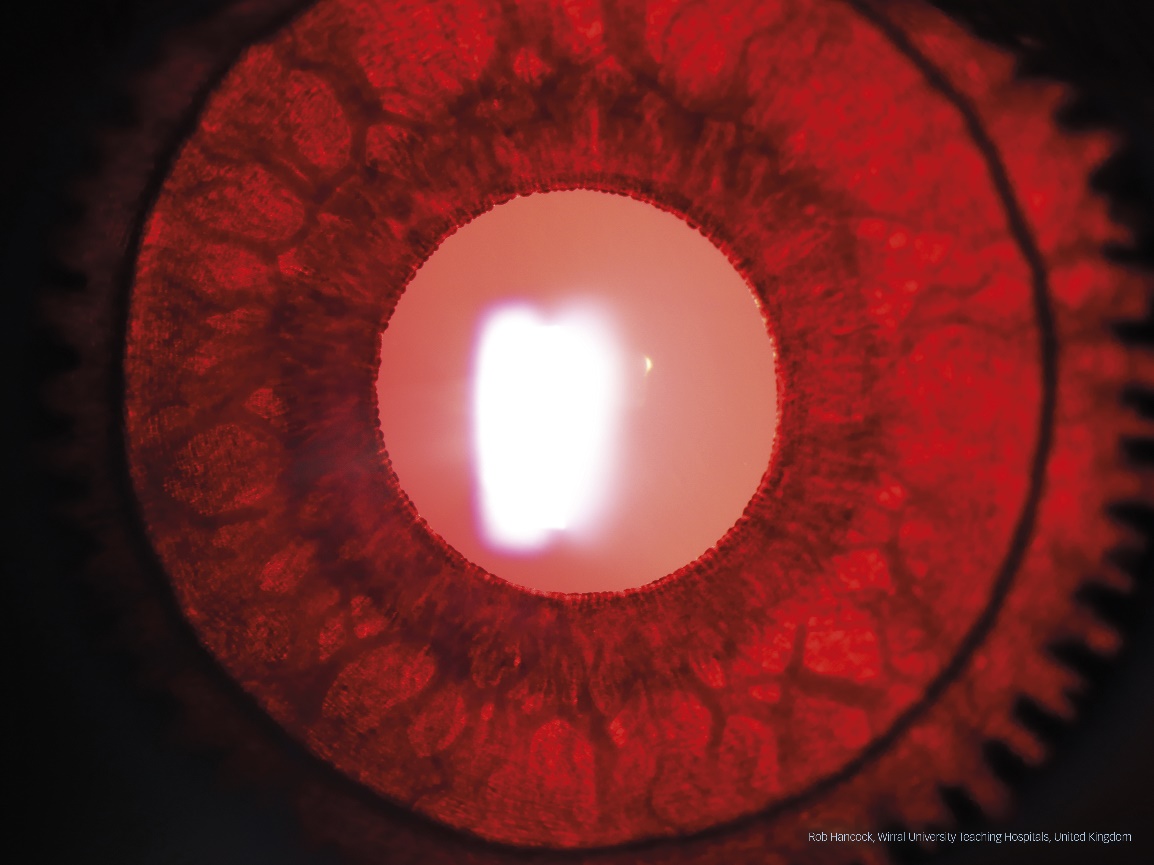

Second place has been awarded to Rob Hancock from Wirral University Teaching Hospitals in Wirral, UK. His image, also taken on a Haag-Streit BX 900 slit lamp, displays a patient with Ocular Albinism and has been captured with iris transillumination technique. The image has been selected by the jury for being crisp, detail-rich and showing a high level of contrast. Mr. Hancock will receive a Nikon Z fc Double Zoom Kit as 2nd prize.

2nd place: Image by Rob Hancock from Wirral University Teaching Hospitals in Wirral, UK showing a patient with Ocular Albinism